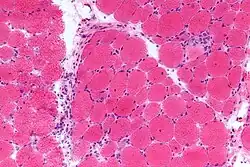

- Examining a muscle biopsy under a microscope and finding mononuclear white blood cells between the muscle cells, and finding abnormal muscle cell degeneration and regeneration, dying muscle cells, and muscle cells being consumed by other cells (phagocytosis)